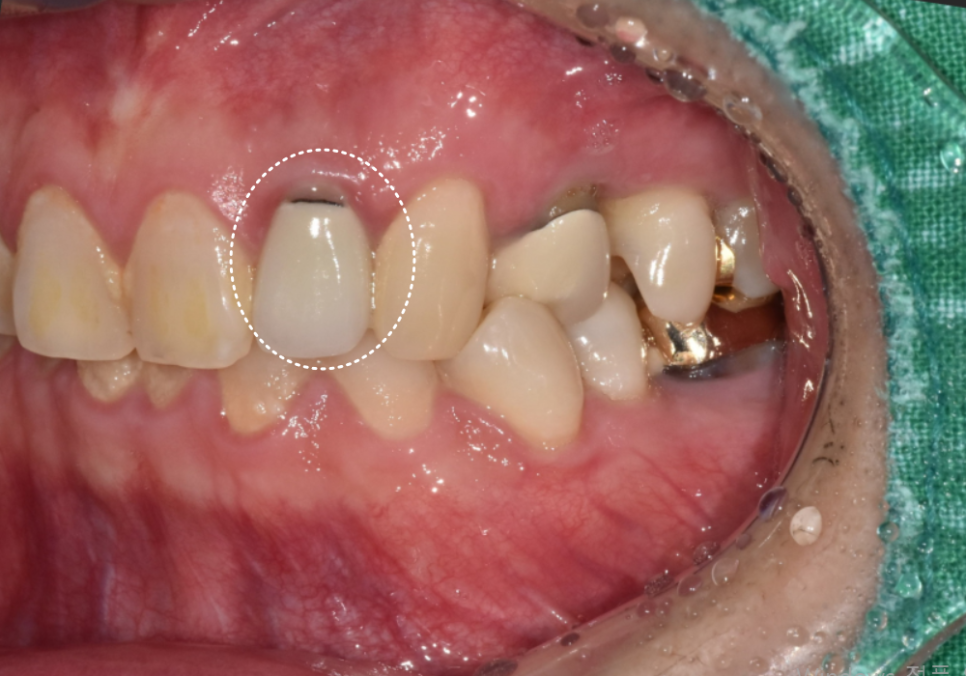

열 번의 소독이 끝난 후

다시 사진을 찍어보았는데요~

까맣게 비어있던 공간이 어떻게 변했을까요?

231129 (전) 240215 (후)

놀랍게도 구멍이 뻥 뚫린 것처럼 보였던

염증 부위가

이제는 거의 회복되어 뼈가 단단하게

차오른 것을 확인할 수 있었습니다.

환자분께서 느끼시는 증상도 많이 좋아지셔서

신경치료를 마무리해드렸어요.

깨끗해진 신경관을

생체 친화적인 재료로 꼼꼼히 메운 뒤,

240424

지르코니아 크라운을 씌워

치료를 마무리했습니다. ^^